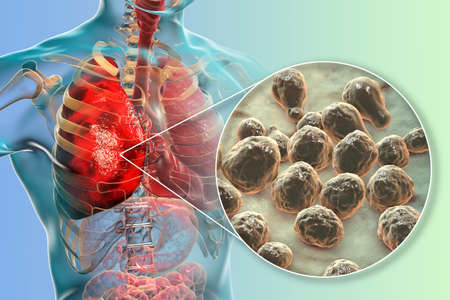

Pulmonary cryptococcosis, invasion of a lung tissue by yeast fungi Cryptococcus neoformans with closeup view of the fungi, 3D illustration. complication